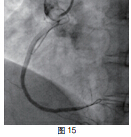

患者RCA为完全闭塞病变,用6F.EBU 3.5导引导管经股动脉对侧造影显示间隔支到RCA远端的侧枝循环,如正向无法开通右冠状动脉可改逆向开通。用JR6F-4导引导管两条pilot-50导引导丝在微导管支持下,用平行导丝技术通过闭塞病变(图3)。分别用Sprinter 1.5 mm×15 mm和2.5 mm×15 mm球囊扩张后RCA开口出现严重夹层,在RCA近端置入Partner 3.0 mm×36 mm支架(图4)。但支架远端仍有严重狭窄,IVUS证实RCA全程弥漫病变,用原2.5 mm球囊扩张后支架远端后,支架远端出现螺旋夹层。拟通过近端支架置入另一Partner 2.75 mm×36 mm支架,但支架无法通过近端支架,头端卡在第一个支架内,在反复用力推送过程中导引导管、导丝自RCA中脱出、将支架球囊弹出,支架球囊撤出体外后发现支架已脱落。透视RCA开口至桡动脉全程,及导引导管内,未发现脱落支架。迅速将原JR4导引导管到位,置BMW导丝到RCA远端,保证RCA开通(图5),IVUS证实导丝全程在真腔内。用原2.5 mm球囊扩张RCA远端以便器械通过(图6)。血管内超声检查提示RCA中段螺旋夹层,撕裂深及血管外膜(图7)。右冠近端支架膨胀、贴壁良好(图8)。将超声导管回撤至右冠状动脉开口处,可见脱落支架卡在右冠状动脉近端支架开口处(图9)。拟取出支架,为预防取出支架过程中RCA急性闭塞,在RCA远端置入BuMA 2.5 mm×30 mm和3.0 mm×30 mm支架,近端支架和原RCA开口处支架未连接(图10)。将Snare圈套器经原作为对侧造影的6F.EBU 3.5导引导管伸出(图11),调整位置,将脱落的支架套住。同时将RCA内的导丝保留,RCA近端支架内预置一3.0 mm×10 mm高压球囊,以保护在取出脱落支架时RCA开口处支架不受影响(图12)。在回撤圈套器时遇到较大阻力,反复推拉,在取出脱落支架的同时将置入RCA开口已释放的的Partner 3.0 mm×36 mm支架带出(图13~14)。RCA开口出现螺旋夹层,但未闭塞。立刻重新置入导丝,IVUS证实导丝在真腔内,在RCA近端分别置入BuMA3.0 mm×25 mm和3.5 mm×20 mm支架,RCA无残余狭窄,血流TIMI3级(图15)。